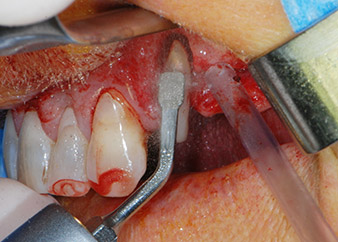

Zunächst wurde in einem Versuch, das Paro-Endo-Problem zu lösen, an der verbleibenden Wurzeloberfläche ein vorsichtiges Debridement mit einem piezochirurgischen Gerät vorgenommen (Piezomed, W&H) (Abb. 4); dann wurde der Apex mit dem gleichen Instrument im Sinne einer WSR abgetragen, um das verbleibende infizierte apikale Gewebe zu entfernen (Abb. 5). Eine retrograde Füllung war nicht notwendig, da die orthograde Füllung gerade revidiert worden war.

Vor der Insertion der Implantate wurde infiziertes Weichgewebe im Implantationsbereich und um das Abutment mit einem Instrument entfernt, das laut Hersteller primär zur Knochenbearbeitung und zum Sammeln von Knochenspänen vorgesehen ist (Piezomed, Einsatz B5) (Abb. 6 und 7).